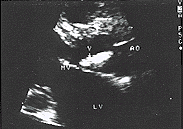

主动脉无冠瓣上2.5cm的赘生物,舒张期返入左室流出道内

图1 左室长轴切面